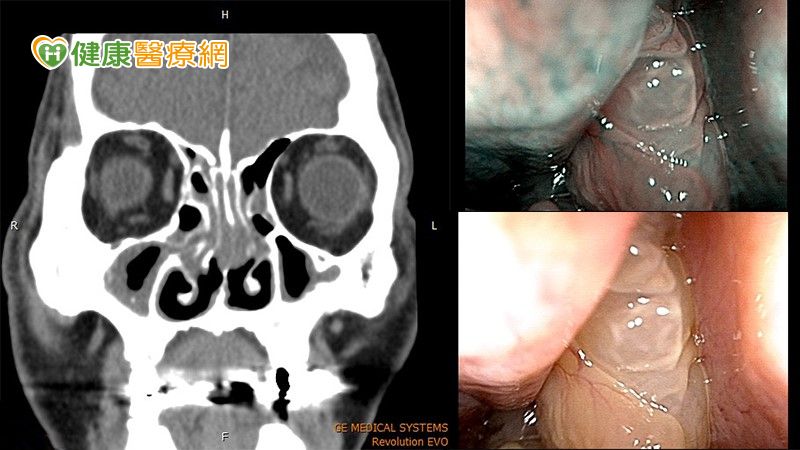

鼻塞季節變換時期,常常成為民眾到耳鼻喉科就診的原因,桃園一位45歲的張先生,因鼻塞問題嚴重影響到夜間睡眠,甚至要張嘴才能呼吸,感到十分不便,特別從桃園北上至雙和醫院找巫承融醫師治療,經醫師內視鏡檢查後發現,右側的鼻孔後側被肥大的鼻息肉阻塞,導致氣流無法通過,還發現鼻中隔彎曲與雙側下鼻甲肥厚,導致鼻子雙側都有鼻塞的情況。張先生與巫承融醫師討論後,決定接受單側功能性鼻竇炎內視鏡手術,以及雙側微創鼻中隔鼻道成型手術,順利將鼻息肉完全清除,且術中搭配膠原蛋白基質粉,有效促進傷口癒合,緩和術後不適,終於解決多年的鼻塞困擾。

鼻息肉阻塞常好發於男性,隨時間可能會增生而變嚴重,有時會合併鼻道、鼻中隔結構異常,長期鼻塞也會連帶影響睡眠品質、氧氣量不足,導致整天都有缺氧狀況,並引起頭痛頭暈,且產生口臭、口乾、喉嚨痛等症狀,造成生活諸多不便。